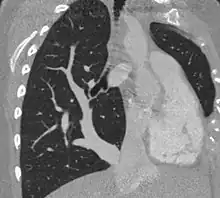

Scimitar syndrome chest CT | |

The diagnosis is made by transthoracic or transesophageal echocardiography and selective pulmonary angiography.[5] More recently by CT angiography or MR Angiography.

Pulmonary angiography demonstrates anomalous arterial supply to right lower lobe.[5]